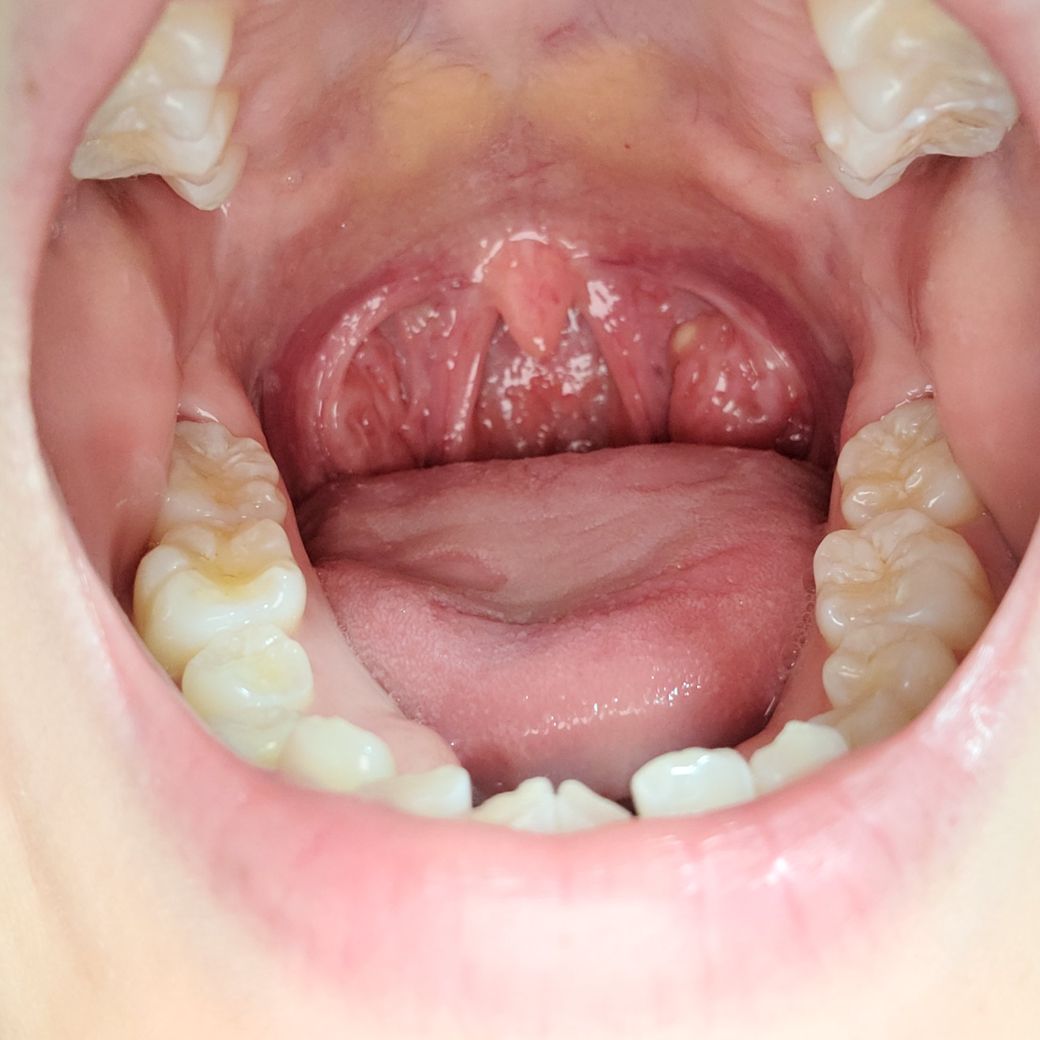

편도가 한 쪽만 커져 있고 덩어리 보이는데 괜찮을까요? (사진 첨부)

오른쪽 편도만 더 크고 하얀 덩어리가 보여서 걱정됩니다..

병원에선 콜레스테롤 덩어리라고 하는데 인터넷엔 같은 케이스가 안나와서 병원을 다녀와서도 신경쓰이네요..

현재 편도나 목이 아프진 않습니다

사진상으로 보았을때 편도의 혹(양성종양) 으로 보입니다. 악성으로 보이지 않으니 걱정 안하셔도 됩니다.